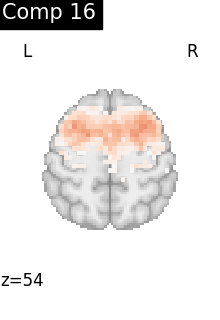

One plot of each component

for i, cur_img in enumerate(iter_img(dictlearning_components_img)):

plot_stat_map(

cur_img,

display_mode="z",

title=f"Comp {int(i)}",

cut_coords=1,

vmax=0.1,

vmin=-0.1,

colorbar=False,

)